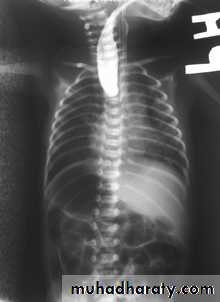

Gas in the wall of bowel in neonates, whatever its shape, is diagnostic of necrotizing enterocolitis